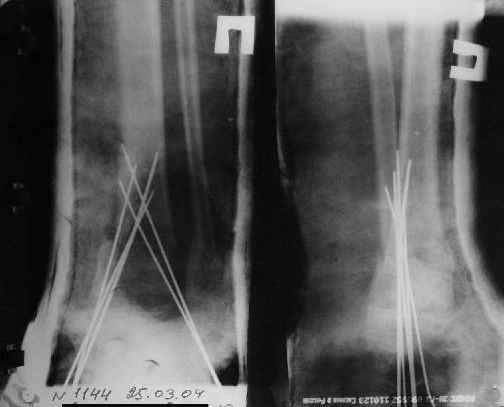

Операции: 1 Клиновидная резекция на вершине деформации м\берцовой кости.

2 Тугоподвижный ложный сустав н\3 б\берцовой кости. Рубцы выполняющие пространство между отломками, канал проксимального отломка иссечены.

Одномоментное устранение деформации, остеосинтез Г-образной пластиной.

Пластика по Хахутову.

Заживление проксимальной части раны вторичным натяжением без нагноения. Рана зажила. Спицы удалены через 1,5 недели после операции.

Особого смысла в них не было.

Учитывая фон (интеллект, etc) гипсовая повязка.

A> Операции: 1 Клиновидная резекция на вершине деформации м\берцовой кости.

A> 2 Тугоподвижный ложный сустав н\3 б\берцовой кости.

Т.е. на фоне некоторого наверняка имевшегося укорочения голени

произвели ее дополнительное укорочение?

Или как?

A> Спицы удалены через 1,5 недели после операции.

A> Особого смысла в них не было.

Не было. Можно было, если особенно хотелось, провести одну

интрамедулярно...

Фиксация

Нашел в комп-ре схожий случай:

1) з/репозиция, 2) фиксация 2 спицами, 3) аппарат, 4) фиксационные

спицы удалены...

См. аттачт.

А можно было наложить аппарат и по поводу ложного сустава...

По крайней мере не было бы укорочения (пусть и в 2 см)...